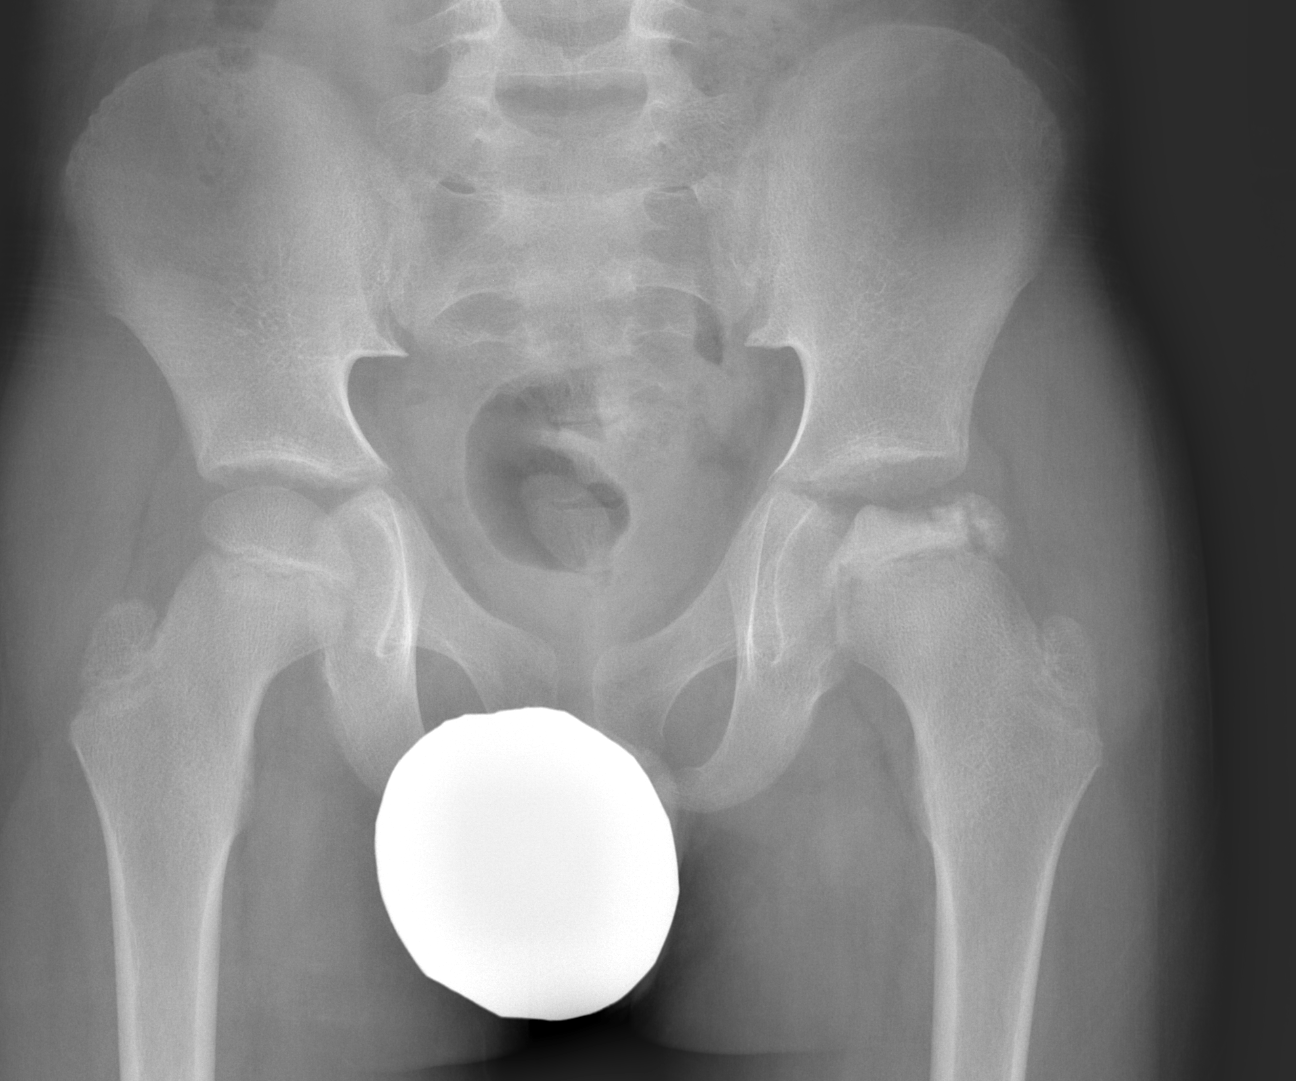

Info Images Findings Impression Reco/Acuity Case Images View Images / Launch Visage Case Notes History 2-month-old presents with decreased right arm movement, increased fussiness, and increased sleepiness for 2 days. Suspected non-accidental trauma. Exam Skeletal survey Prior Study none Dicom View Reference Material

Section 1 Submit Findings CB1550 Findings Skeletal Survey - Technique Check Skull AP/Lat Yes No Cervical and Thoracolumbar spine Yes No Chest X-Ray Yes No Ribs – Left/Right Oblique Yes No Abdominal X-Ray Yes No Pelvis with both hips Yes No Bilateral Humerus, Forearm, Hand Yes No Bilateral Femur, Tibia/fibula, feet Yes No Any additional lateral views of the extremities Yes No The exam is over or under penetrated. Yes No The exam may or may not be limited by overlying structures or soft tissues, body habitus, patient positioning, support devices, or motion. Yes No The area of concern is indicated by the patient, technologist, or care provider. Yes No The area of concern is included on the exam. Yes No Soft Tissues There is soft tissue swelling, indistinctness of fat/muscle planes, gas, or laceration in the area of clinical concern. Yes No There is an effusion, fat pad displacement, or fat fluid level. Yes No There is a radiodense or lucent foreign body. Yes No There are other densities, calcifications, post-surgical changes, or support devices in the soft tissues. Yes No Any support lines/tubes. Yes No Bone There is a break or interruption of the continuity of the cortical or cancellous bone. Yes No There is overriding of the trabeculae with apparent sclerosis. Yes No There is displacement of a fracture fragment. Yes No There is bowing of the bone in addition to the fracture at the apex of the bowed bone concerning for the greenstick. Yes No There is a spiral fracture of the leg concerning for toddler’s fracture. Yes No There is abnormal angulation or bulging of the cortical surface relative to the normal cortex which could be from a buckle or torus fracture. Yes No There is a displaced fragment which may be from avulsion by a tendon, ligament, or joint capsule or from a comminuted or other fracture. Yes No The stress trabeculae or other trabeculae of the cancellous bone are interrupted or otherwise abnormal. Yes No There is subperiosteal or endosteal reaction which could indicate a healing or subacute fracture or other abnormality. Yes No There is hard/soft callus formation. Yes No There is remodeling of the bone. Yes No There is a corner fracture or metaphyseal lesion that could be from nonaccidental trauma. Yes No There are multiple fractures of different ages. Yes No There are vertebral body/spinous process fractures. Yes No There are rib fractures. Location - posterior or lateral. Yes No There is scapular/sternal fracture. Yes No There are fractures of the digits. Yes No There are wormian bones. Yes No There are intrasutural bones. Yes No There is metaphyseal abnormality (lucencies, increased density, erosion) which may be from something other than injury such as stress, metabolic disease (e.g. rickets with loss or distortion of the zone of the provisional calcification), neoplasm (e.g. leukemia), heavy metals, inflammation, or infection. Yes No There are metaphyseal spurs. Yes No There are bony deformities involving multiple bones. Yes No The bones are gracile. Yes No There are non-healing fractures. Yes No There is/are focal or multifocal lytic/lucent, blastic/sclerotic or mixed density lesion(s) or other abnormality. Yes No Overall bone density is increased or decreased with or without thinning or thickening of the cortical or cancellous bone. Yes No Growth plates, ossification centers, apophyses The growth plate(s) is/are abnormal. Yes No There is widening of the physis from a fracture with or without displacement of the epiphysis (Salter-Harris I). Yes No There is a fracture through the physis which then extends into the metaphysis with or without angulation or displacement (S-H II). Yes No There is a fracture through the physis which then extends into the epiphysis and is intra-articular, with or without angulation or displacement (S-H III). Yes No There is a fracture through the metaphysis, physis, and epiphysis which extends into the joint space with or without angulation or displacement (S-H IV). Yes No There is narrowing of the physis from a compression fracture (S-H V). Yes No The apophysis, epicondyle, secondary ossification center, or accessory ossicle is displaced or otherwise abnormal. Yes No The ossification centers are underdeveloped. Yes No Joints and alignment There is an effusion, fat pad displacement, or fat fluid level. Yes No The epiphysis or subchondral bone is fractured, interrupted, flattened, compressed, impacted, displaced, or otherwise abnormal. Yes No There is an intra-articular loose body or chondrocalcinosis. Yes No The joint is widened, narrowed, dislocated, malaligned, or incongruent. Yes No There is pseudoarthrosis. Yes No Other findings There are developmental changes or other anatomic variants or other existing conditions that may or may not be contributing to symptoms which can or should be further evaluated non-emergently or are otherwise incidental. Yes No The remainder of the exam is abnormal for age. Yes No The lungs show focal airspace opacity. Yes No There is pneumothorax. Yes No There is organomegaly. Yes No There is intra-abdominal calcification. Yes No There is displacement of the bowel loops. Yes No There is free intraperitoneal air. Yes No The bowel loops are dilated/obstructed. Yes No There is paraspinal soft tissue abnormality. Yes No